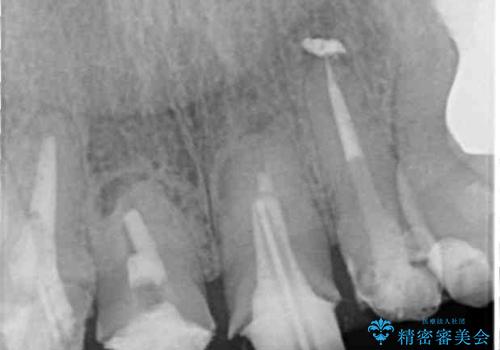

- 仮歯装着後に放置してしまい、恥ずかしいとのことで来院された患者様です。

仮歯が不適合で歯肉が腫脹していたため、しっかりと調整した新しい仮歯にして腫れを改善した上で、オールセラミッククラウンにて補綴することとしました。

日頃の歯磨きをしっかりと行ってくださるので、新しい仮歯に変えてから速やかに歯肉の状態が改善されました。

歯肉からの出血がほとんどないため精度の良い型取りができ、非常に適合の良い補綴治療を行うことができました。